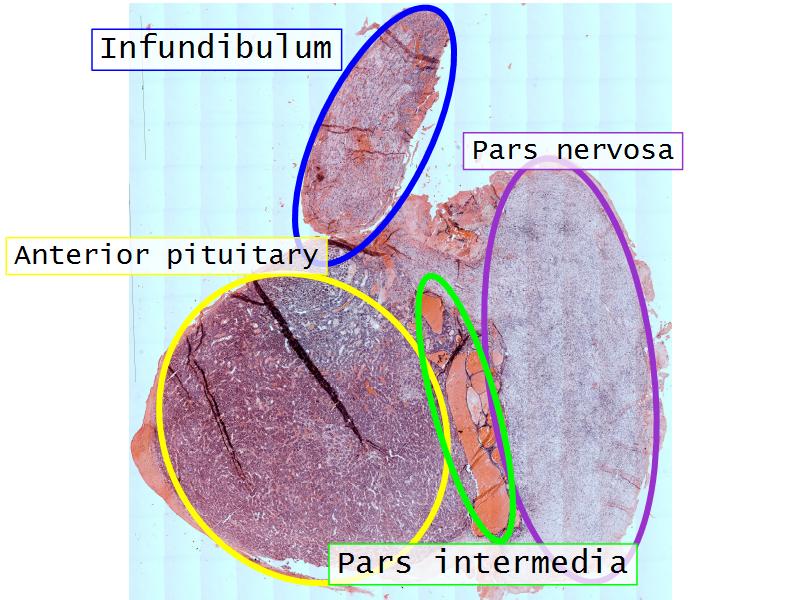

- Slide 52: Pituitary gland

Pituitary gland